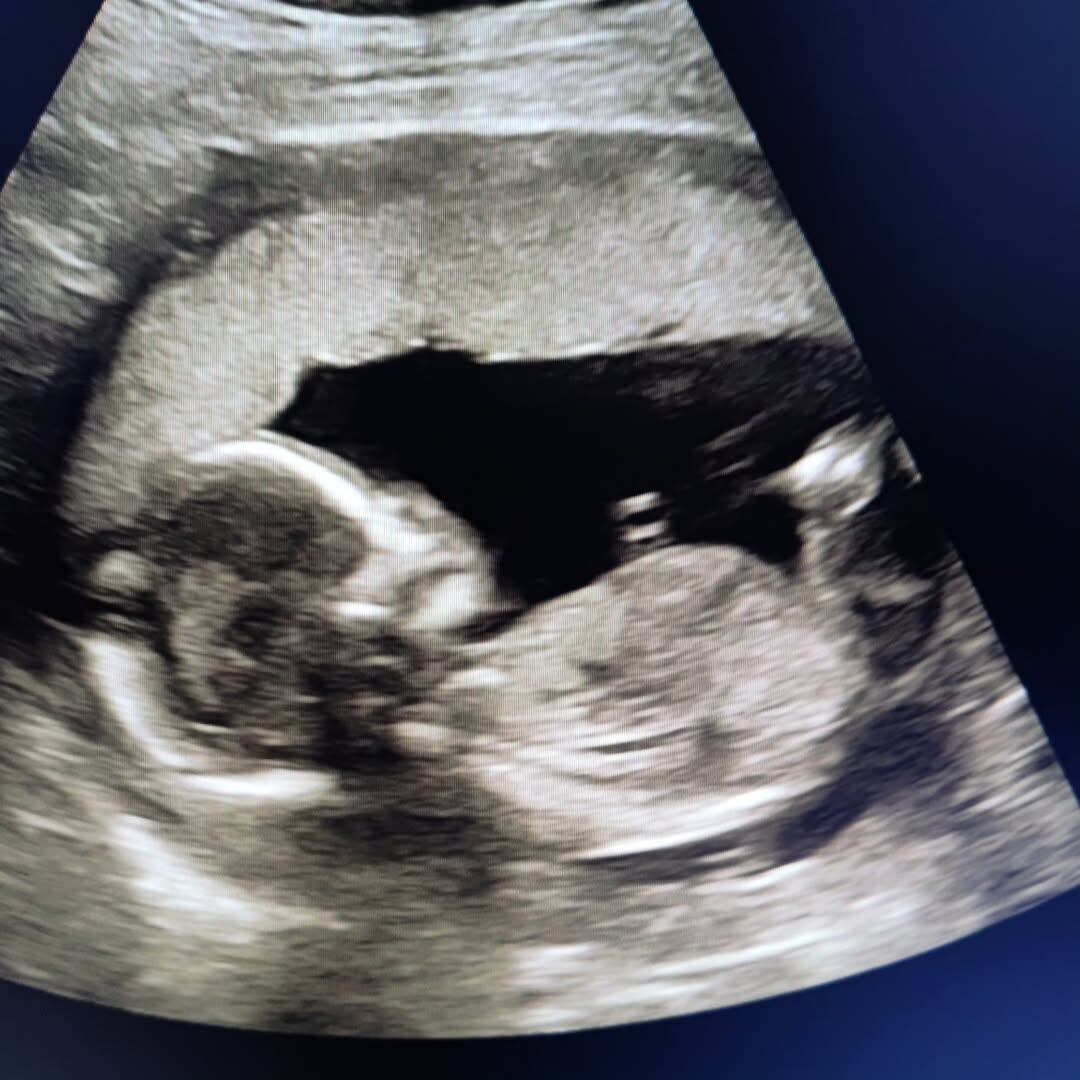

En su última publicación en Instagram, la jueza compartió una imagen de la ecografía de su hija, nacida hace dos meses, acompañada del mensaje: “¡Te amo Mohammed!”.